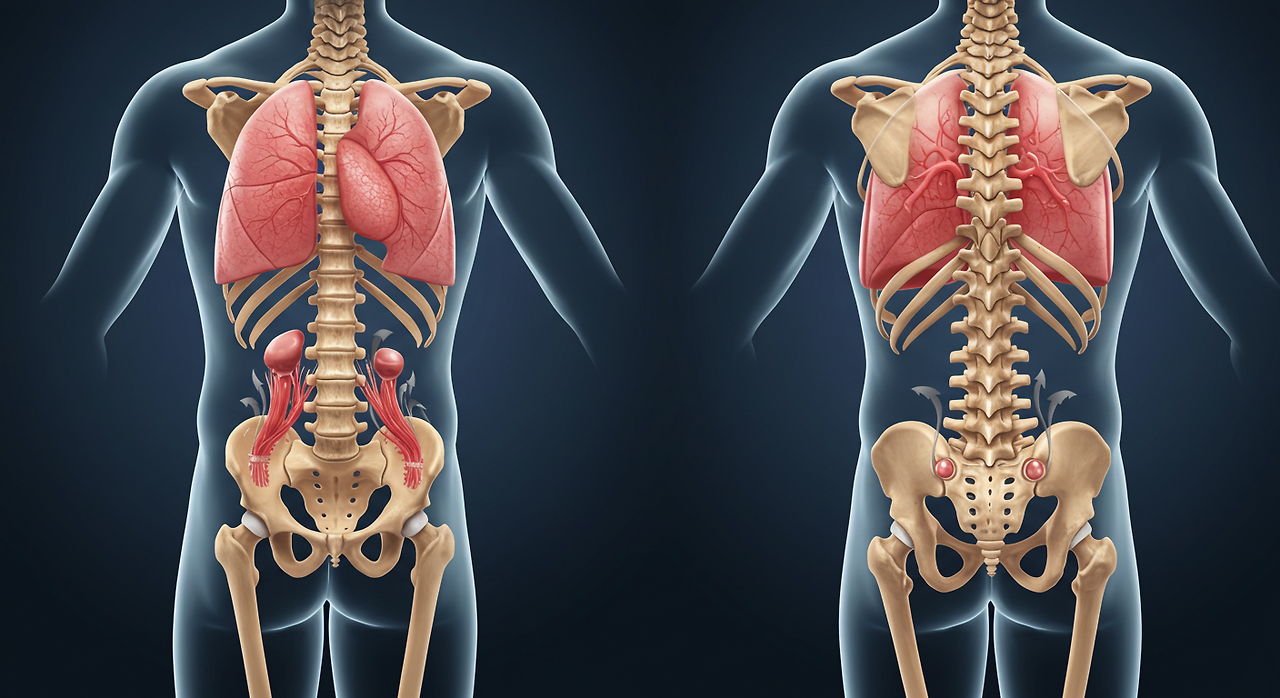

척추 하부는 우리 몸의 중심을 잡아주는 **하중 지지대 역할**을 하며,

**골반, 다리, 신경, 장기 기능과도 밀접한 관련**이 있습니다.

그래서 **허리와 골반에 문제가 생기면 전신 건강에도 악영향을 줄 수 있음!** 😱

## 🏋️♂️ 척추 하부(요추 & 천추)의 역할

📌 **요추(Lumbar Spine) & 천추(Sacrum)란?**

✔ **요추(L1~L5)** → 허리 부분에 위치, 몸의 하중을 지탱

✔ **천추(S1~S5, 꼬리뼈 포함)** → 골반과 연결, 하반신 신경 조절

❌ **허리 & 골반에 문제가 생기면?**

👉 **신경이 눌리고, 다리가 저리고, 장기 기능까지 영향을 받을 수 있음!**